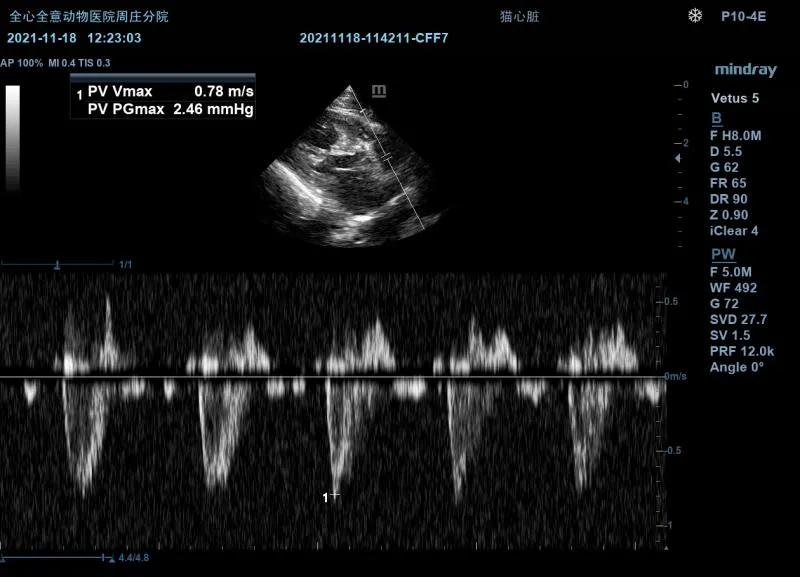

超声检查:

右侧左室流出道观:

左室不均匀性增厚,心尖最为明显。可见乳头肌增大异常,腱索连接异常,室间隔基部异常向左心室内增大,导致左室流出道前窄后宽。左心房主观增大。color模式下收缩期可见左室流出道以红色为主的花色血流信号,左房可见蓝色为主的花色血流信号。

左侧测量瓣膜口流速正常。